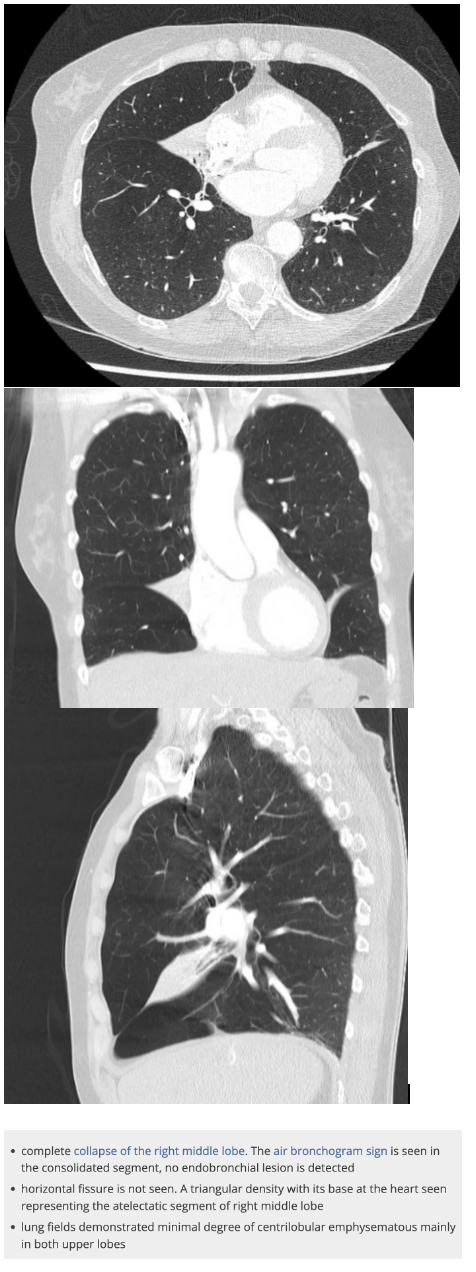

What are the features of RML collapse on CXR?

CXR features: (7)

R mid to lower air space consolidation – can be subtle in PA, so lateral CXR can help

Horizontal fissure no longer visible

Obscured R heart border

Elevated R. hemidiaphragm

Crowding of R sided ribs

Mediastinum shifted to the right

Displaced R hilum

Lateral CXR:

Triangular opacity projecting over cardiac shadow

Horizontal fissure not visible

What are the features of RML collapse on CT scan

CT features: (4)

Triangular opacification abutting R heartborder, thinner at the hilum in axial image

Horizonal fissure rotates anteromedially

Oblique feature bows anteriorly

RUL rotates anterolaterally and RLL rotates posterolaterally and meets lateral to the collapsed RML